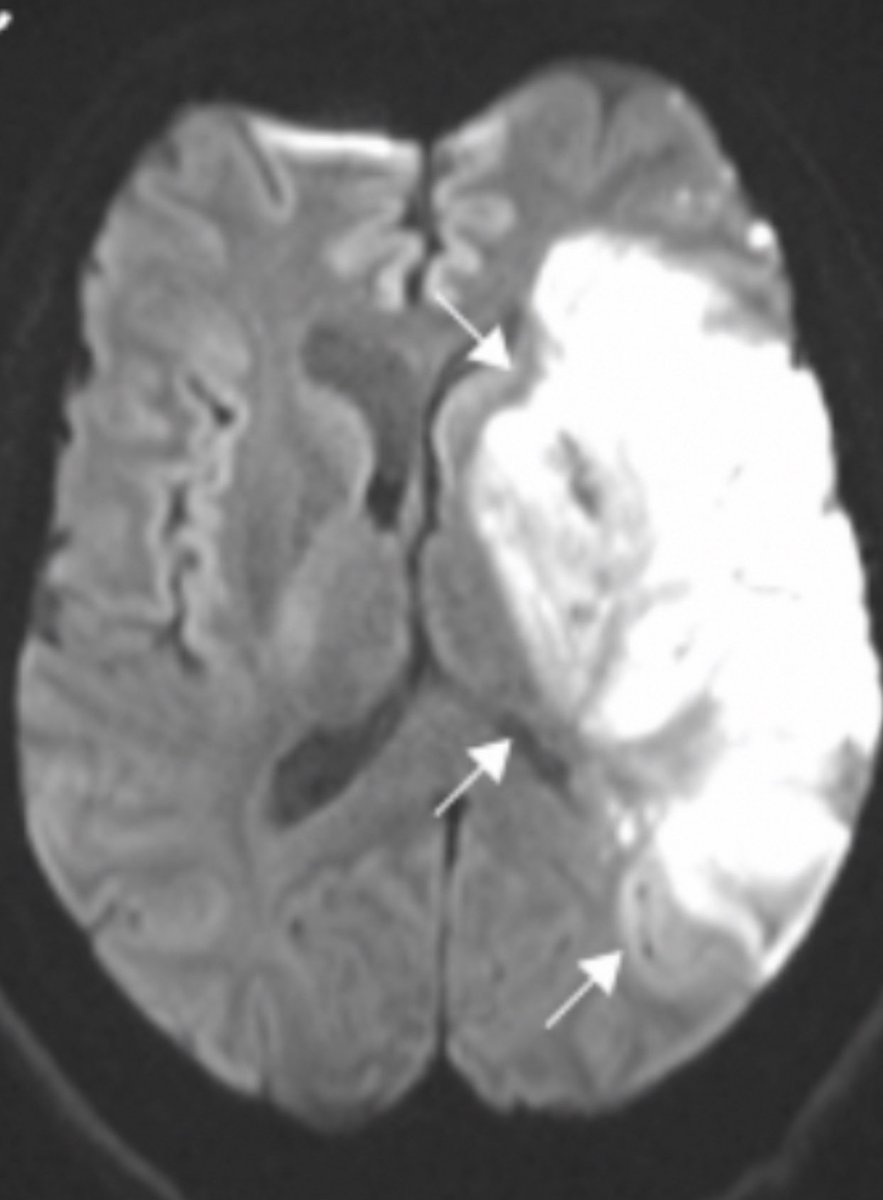

Recently published large study of brain MRI in acute #COVID shows vascular phenomena are common.

bit.ly/4pX0Hu3Image

458 brains studied

First wave of pandemic (so not applicable to later/current variants)

Most common finding = ischaemic infarct (stroke)

See image B-F Image

Large vessel strokes more common than small vessel

The large white area is abnormal Image